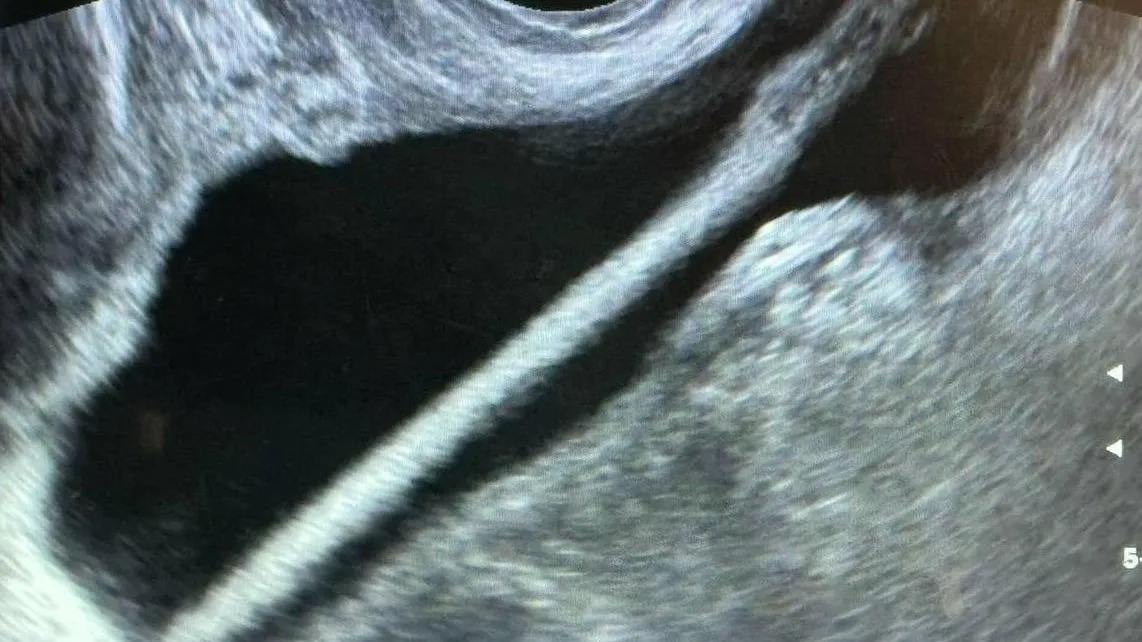

Женщину госпитализировали в урологическое отделение. Сначала ей сделали УЗИ, затем провели операцию. Карандаш из организма женщины был удален с помощью эндоскопа.